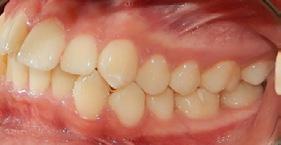

desviada 2 milimetros a la derecha, OD 12 y 22 palatinizados, en la Figura 9 vemos la clase III molar izquierda y derecha y la clase III canina bilateral, en la Figura 10 apreciamos las arcadas de forma triangular.

Resultados

Se lograron los objetivos planteados, durante el tiempo de tratamiento de 3 años y 10 meses, en la Figura 11 se puede observar que del lado derecho se obtuvo la clase I molar y se mantuvo la clase III molar izquierda, clase I canina bilateral, la línea media superior coincidente e inferior desviada 0.5 milímetros a la derecha al final del tratamiento, adecuada intercuspidación, en la Figura 12 la forma oval de la arcada superior e inferior.